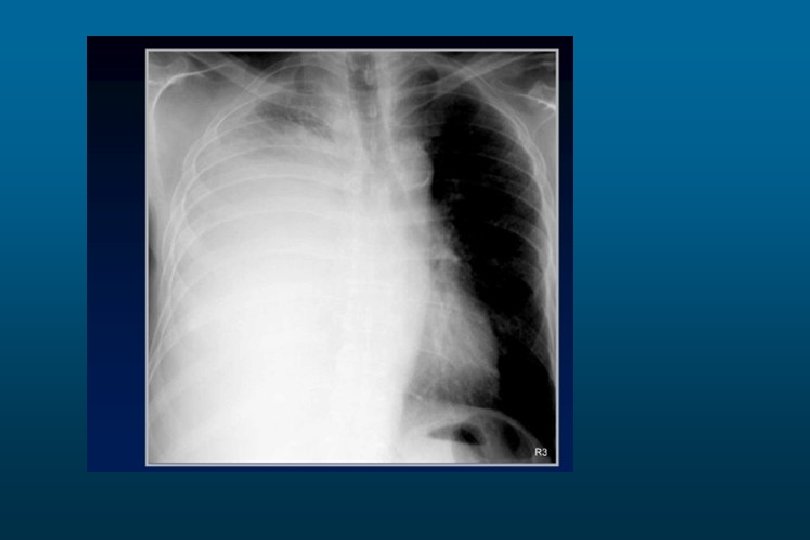

Pneumothorax

Pneumothorax.